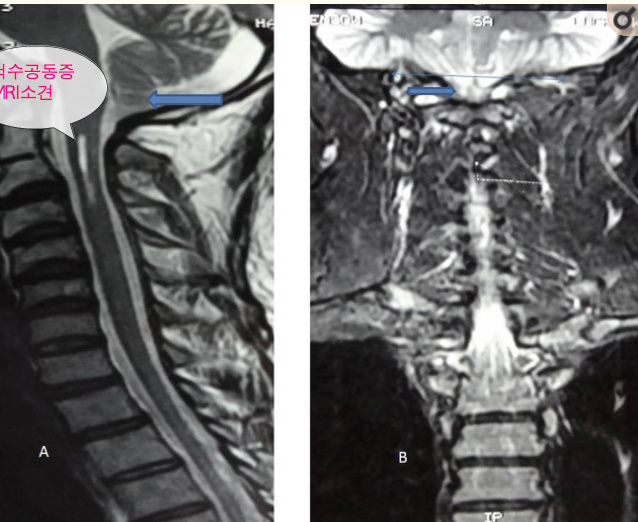

척수공동증은 특징적으로 척수에 물이 찬 공동이 발생하는 것으로 방사선 촬영을 해 보면 이것을 확인 할 수 있습니다. 좀 더 정확한 영상을 얻기 위하여 전산화 단층 촬영술(CT)이나 자기공명영상(MRI)과 같은 이미지 촬영을 해볼 수 있습니다.

척수공동증(Syringomyelia)은 척수(Spinal cord) 안에 물이 찬 공동(Syrinx)이 생기는 병으로, 이 공동이 시간이 지나면서 점차 커지면서 척수신경을 압박하여 척수신경을 손상시키게 되므로 증상이 발생하게 됩니다. 척수에 공동이 생기는 원인은 다양하지만 특별한 원인을 알 수 없는 경우도 많습니다. 공동은 척수신경의 중심부에서 생기기 시작하여 바깥쪽으로 커지며 척수 전부를 채울 만큼 긴 공동을 만들기도 하는데, 공동이 늘어나게 되면서 다리, 팔, 등, 어깨를 조절하는 신경에 영향을 미칠 수 있습니다. 그러면 환자는 영향을 받은 부위의 아픔을 느끼게 되고 힘이 빠지거나, 뜨겁고 찬 것을 구분하지 못하게 될 수도 있습니다. 증상은 공동이 척추 어떤 곳에서 생기는지와 시간이 지나면서 얼마나 커지는지에 따라서 사람마다 다양하게 나타날 수 있습니다. 증상은 종종 대부분 천천히 발생하나, 일부 갑자기 발생하는 경우도 있으며, 증상을 수술 등의 방법으로 치료하지 않는다면 신경이 영구적으로 손상될 수 있고 만성적인 심한 통증으로 발전 할 수도 있습니다.